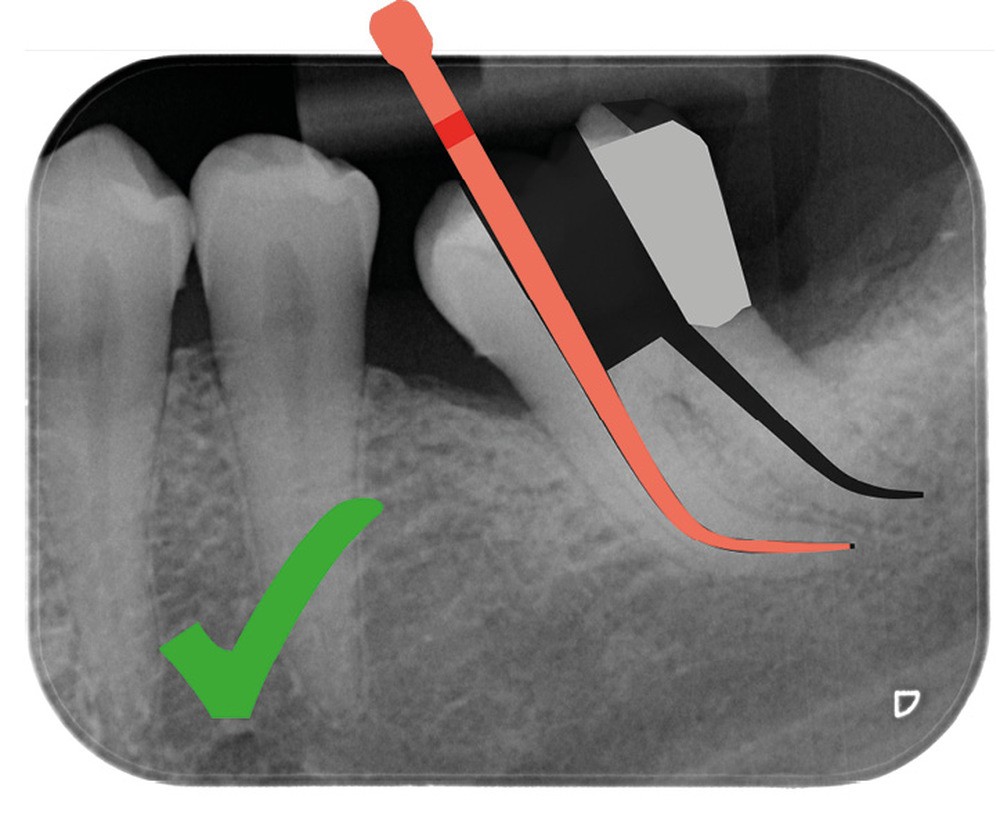

Aussi petite que possible, aussi large que nécessaire

Une cavité d’accès moderne, dictée par l’anatomie et la pathologie de la dent, optimiserait à la fois les pronostics endodontiques et biomécaniques et donc la longévité de la dent sur l’arcade (patient-centered dentistry ou dentisterie centrée sur le patient) (fig. 5).